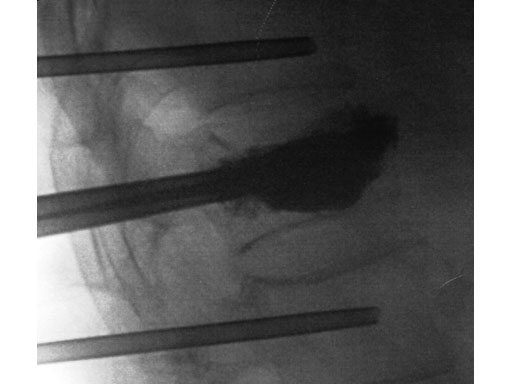

A 78-year-old man with back pain after a simple fall. An MRI showed a subacute fracture with a collapsed vertebral body of L1. A VB S was used for height restoration. The patient was pain-free immediately after the intervention.

Fig 1-4 Intraoperative images.